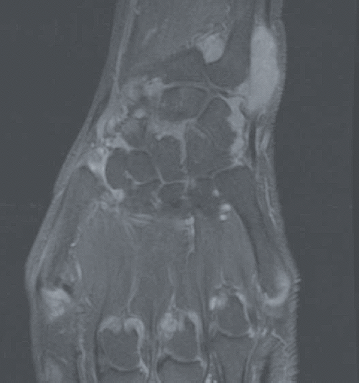

La polyarthrite rhumatoïde (PR) est une maladie auto-immune mais dans laquelle les auto-anticorps que sont le facteur rhumatoïde (FR) et les anticorps anti-peptides citrullinés (ACPA ; également appelés anti-CCP) ne sont pas constants : les PR appelées « séropositives » (FR+ et/ou ACPA+, qu'il conviendrait mieux de dénommer immuno-positives) représentent 75 à 80% des PR. Il reste donc 20 à 25% des PR séronégatives (FR- et ACPA-) dont la reconnaissance précoce est rendue plus difficile par l'utilisation des critères de classification européens-américains ACR/EULAR 2010 où le poids des auto-anticorps est très important (Tableau 1). La question de savoir s'il existe une seule PR avec deux visages ou deux maladies de physiopathologie différente reste débattue. Dans le diagnostic (et le suivi) de ces formes séronégatives, comme dans les formes séropositives, l'intérêt de l'échographie articulaire a été récemment souligné. L'IRM a également un intérêt pour la mise en évidence des synovites mais est ciblée sur une articulation ou un groupe articulaire alors que l'échographie permet une analyse de très nombreuses articulations (Figure 1). Un autre axe d'intérêt est représenté par les formes très précoces de PR, avec cliniquement de simples arthralgies mais associées à des auto-anticorps (FR/ACPA), situation où des essais d'intervention thérapeutique ont été menés récemment où sont en cours.

Figure 1. Exemple d'IRM du poignet et des métacarpo-phalangienne au cours de la PR en poussée